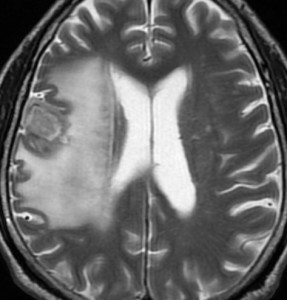

定位放射線治療前

典型的な脳転移のMRIです。腫瘍は,リング状にガドリニウム増強され,内部が腫瘍壊死になっています。腫瘍周囲の脳浮腫がとても強いのが転移の特徴的画像所見(右側のT2強調画像)です。この転移巣に対して,35グレイ・5分割の定位放射線治療が加えられました。

定位放射線治療後

治療は奏功して,腫瘍は縮小して周囲の脳浮腫(右側)も軽減しています。